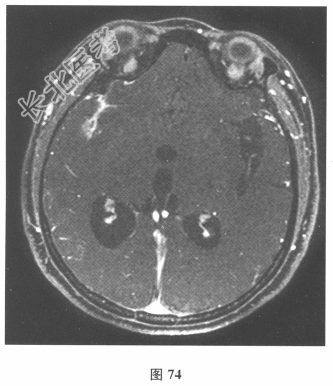

- 简答题3、患者入院后复查腰椎穿刺:脑脊液抗酸染色(-),墨汁染色(-),嗜酸性粒细胞比例增高,淋巴细胞体积较大。血及脑脊液弓形虫抗体均(-),血及脑脊液囊虫IgG抗体均(+),莱姆病抗体(-)。追问病史,曾经食用过“米猪肉”。进一步行颅脑MRI检查见图74、图75。)根据上述患者病史和检查结果,对此患者下一步治疗的药物包括